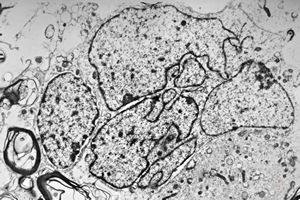

F,49y. | purulent meningitis- meningococcal v.s.